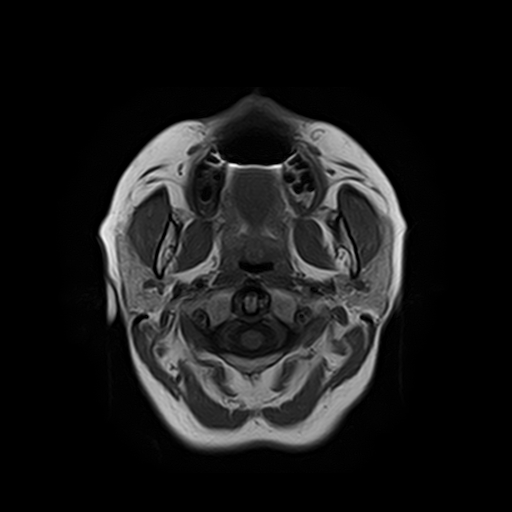

Височно-нижнечелюстной сустав является парным комбинированным суставом и имеет сложное строение. В него входят суставные ямки височной кости, суставные головки нижней челюсти и расположенные между ними хрящевые пластинки – мениски, выполняющие роль амортизаторов.

Чаще всего дисфункция височно-нижнечелюстного сустава обусловлена внутренним повреждением, смещением мениска и суставной головки нижней челюсти. Для определения степени смещения внутрисуставных структур выполняется функциональная проба с проведением МРТ в двух положениях:

Магнитно-резонансная томография является наиболее точным и эффективным методом диагностики поражения височно-нижнечелюстных суставов, так как позволяет получить детальную информацию о состоянии не только костей, но и связочного аппарата, хрящей, менисков, жевательных мышц, окружающих мягких тканей.

При проведении магнитно-резонансной томографии на изображениях визуализируются: височная кость, головка мыщелкового отростка нижней челюсти, суставная щель. Помимо костных структур МРТ позволяет оценить состояние мягких тканей – внутрисуставного диска и связочного аппарата височно-нижнечелюстного сустава, жевательных мышц.